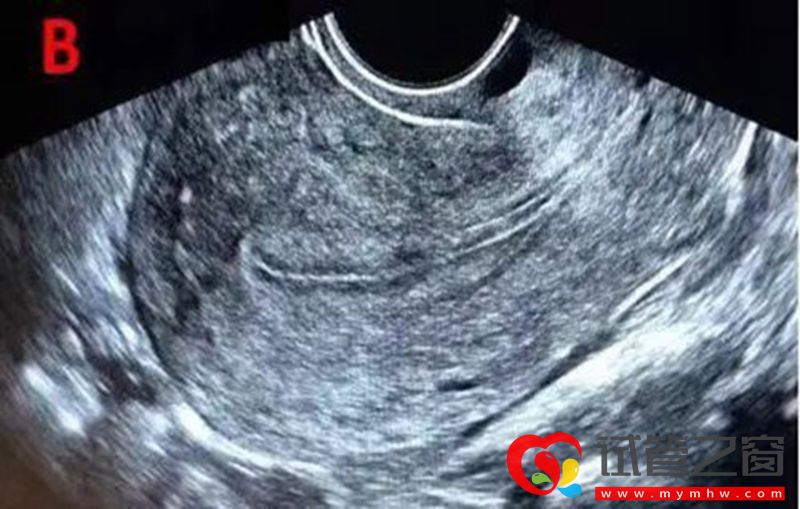

成熟卵泡(月經周期14天左右):卵泡直徑達到18-25mm時,外形飽滿呈圓形或橢圓形,內壁薄而清晰,位置移向卵巢表面并向外突出,如果卵泡一側內壁上探及卵丘(出現率約20%),表現為細小點狀高回聲 ,意味著排卵過程將在24小時內開始。

成熟卵泡消失或原成熟卵泡直徑明顯縮小,形態不規則,壁皺縮,卵泡內透聲差,可見細弱光點,部分女性會出現子宮直腸凹積液,子宮內膜逐漸由A型轉變為C型。